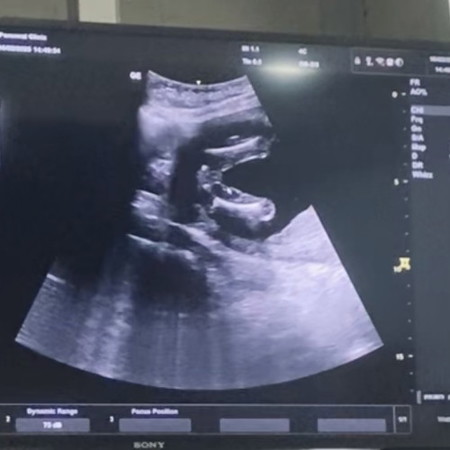

แม่ๆค่ะแบบนี้ผุ้หญิงหรือผุ้ชายค่ะแม่ๆ

ผู้ญค่ะ น้องมีกลีบชัดมากค่ะ🥰

ผู้หญิงชัวร์ๆค่ะ ชัดเจนมาก🥰